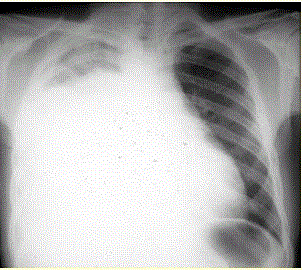

问题  患者男,34岁。进行性胸闷、气促1个月余,伴有干咳、右胸隐痛以及消瘦,无咯血、发热、盗汗、潮热等。 考虑患者目前出现的情况是(提示 为解决患者胸闷、气促症状,给予胸腔插管引流胸腔积液,一次性放出淡黄色胸腔积液约1 800 ml。患者引流后自觉气促症状减轻,但半小时后渐觉胸闷、呼吸困难再次加重,剧咳伴咳大量泡沫样痰。体格检查:端坐呼吸,口唇发绀,双肺满布湿性啰音,心率130次/min,律齐。)

选项 A、急性左心衰竭 B、胸腔内出血 C、胸膜反应 D、医源性气胸 E、急性呼吸窘迫综合征 F、肺复张后肺水肿 G、急性肺血栓栓塞症

答案 F